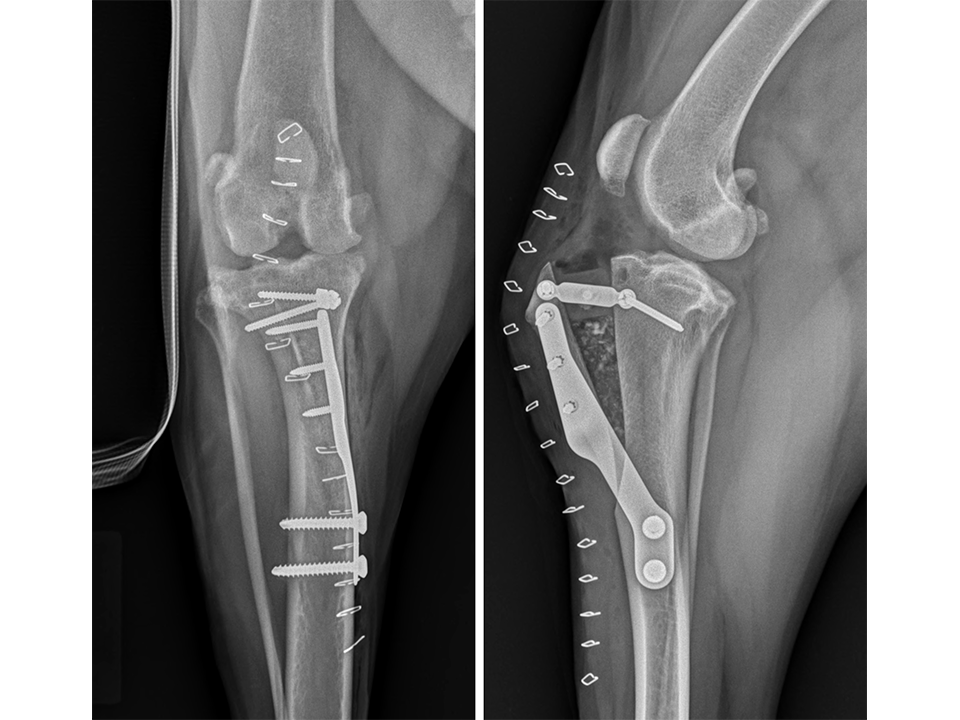

Immediate postoperative radiographs (Fig 7) revealed satisfactory implant and osteotomy positioning. Radiographs obtained 10 weeks postoperatively (Fig 8) showed no evidence of implant-associated complications and partial bone healing within the osteotomy gap. Osteoarthritic changes within the joint were static. Clinically at this stage, mild bilateral pelvic limb lameness was apparent bilateral stifle joint effusion. The left stifle joint was stable in CrTT with no pain response upon stifle joint manipulation.